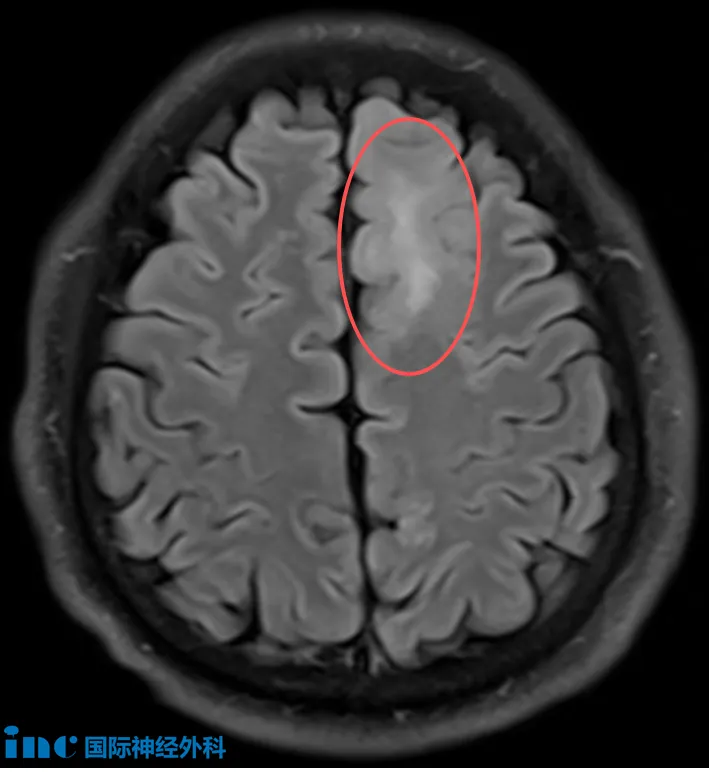

48歲的孫先生,在當?shù)蒯t(yī)院體檢頭顱核磁,發(fā)現(xiàn)左側額葉存在異常信號。為進一步明確診斷,他進行了PET-MRI檢查,結果提示:左額葉近中線異常信號,考慮低級別膠質(zhì)瘤可能性大(脫髓鞘病變不除外)。隨后的頭顱MRI確認了左額葉皮層及皮層下存在邊界不清的異常信號,范圍約41×28mm,增強掃描未見明顯強化。令家屬擔憂的是,孫先生近來已出現(xiàn)記憶力下降的跡象。面對這個超過4厘米、性質(zhì)未明的腦內(nèi)病灶,到底是什么,要不要手術?

“歸根結底,我們從來無法從影像獲得百分之百的確定性。手術是獲得準確診斷的唯一方法。即便影像顯示這是腫瘤,我們?nèi)匀徊涣私饽[瘤的分子特征,而這也是非常重要的。我會盡可能多地切除,但同時我們也不希望損傷或影響功能。”——INC巴教授